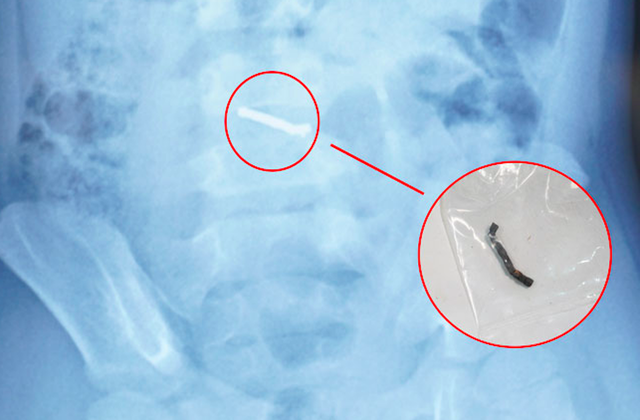

Hình ảnh nam châm dính thành chuỗi trong ổ bụng bệnh nhi. Ảnh: BVCC.

Thanh nam châm dính chặt sau khi được các bác sĩ lấy ra từ bụng bệnh nhi. Ảnh: BVCC.

Từ thông tin gia đình cung cấp về loại đồ chơi có các viên nam châm nhỏ có thể hút vào nhau, các bác sĩ chẩn đoán trẻ đã nuốt phải nhiều viên nam châm trong nhiều thời điểm. Sau khi xác định dị vật có từ tính và không thể tự đào thải ra ngoài, các bác sĩ đã tiến hành phẫu thuật cho trẻ.

Trong quá trình phẫu thuật, các bác sĩ phát hiện nhiều viên nam châm nhỏ dính vào nhau thành một chuỗi, gây thủng ruột. Các bác sĩ phẫu thuật đã tiến hành lấy dị vật, khâu lỗ thủng và đặt dẫn lưu. Sau 4 ngày, bệnh nhi đã sinh hoạt bình thường, bắt đầu được tập ăn trở lại và dự kiến sẽ được ra viện trong một vài ngày tới.